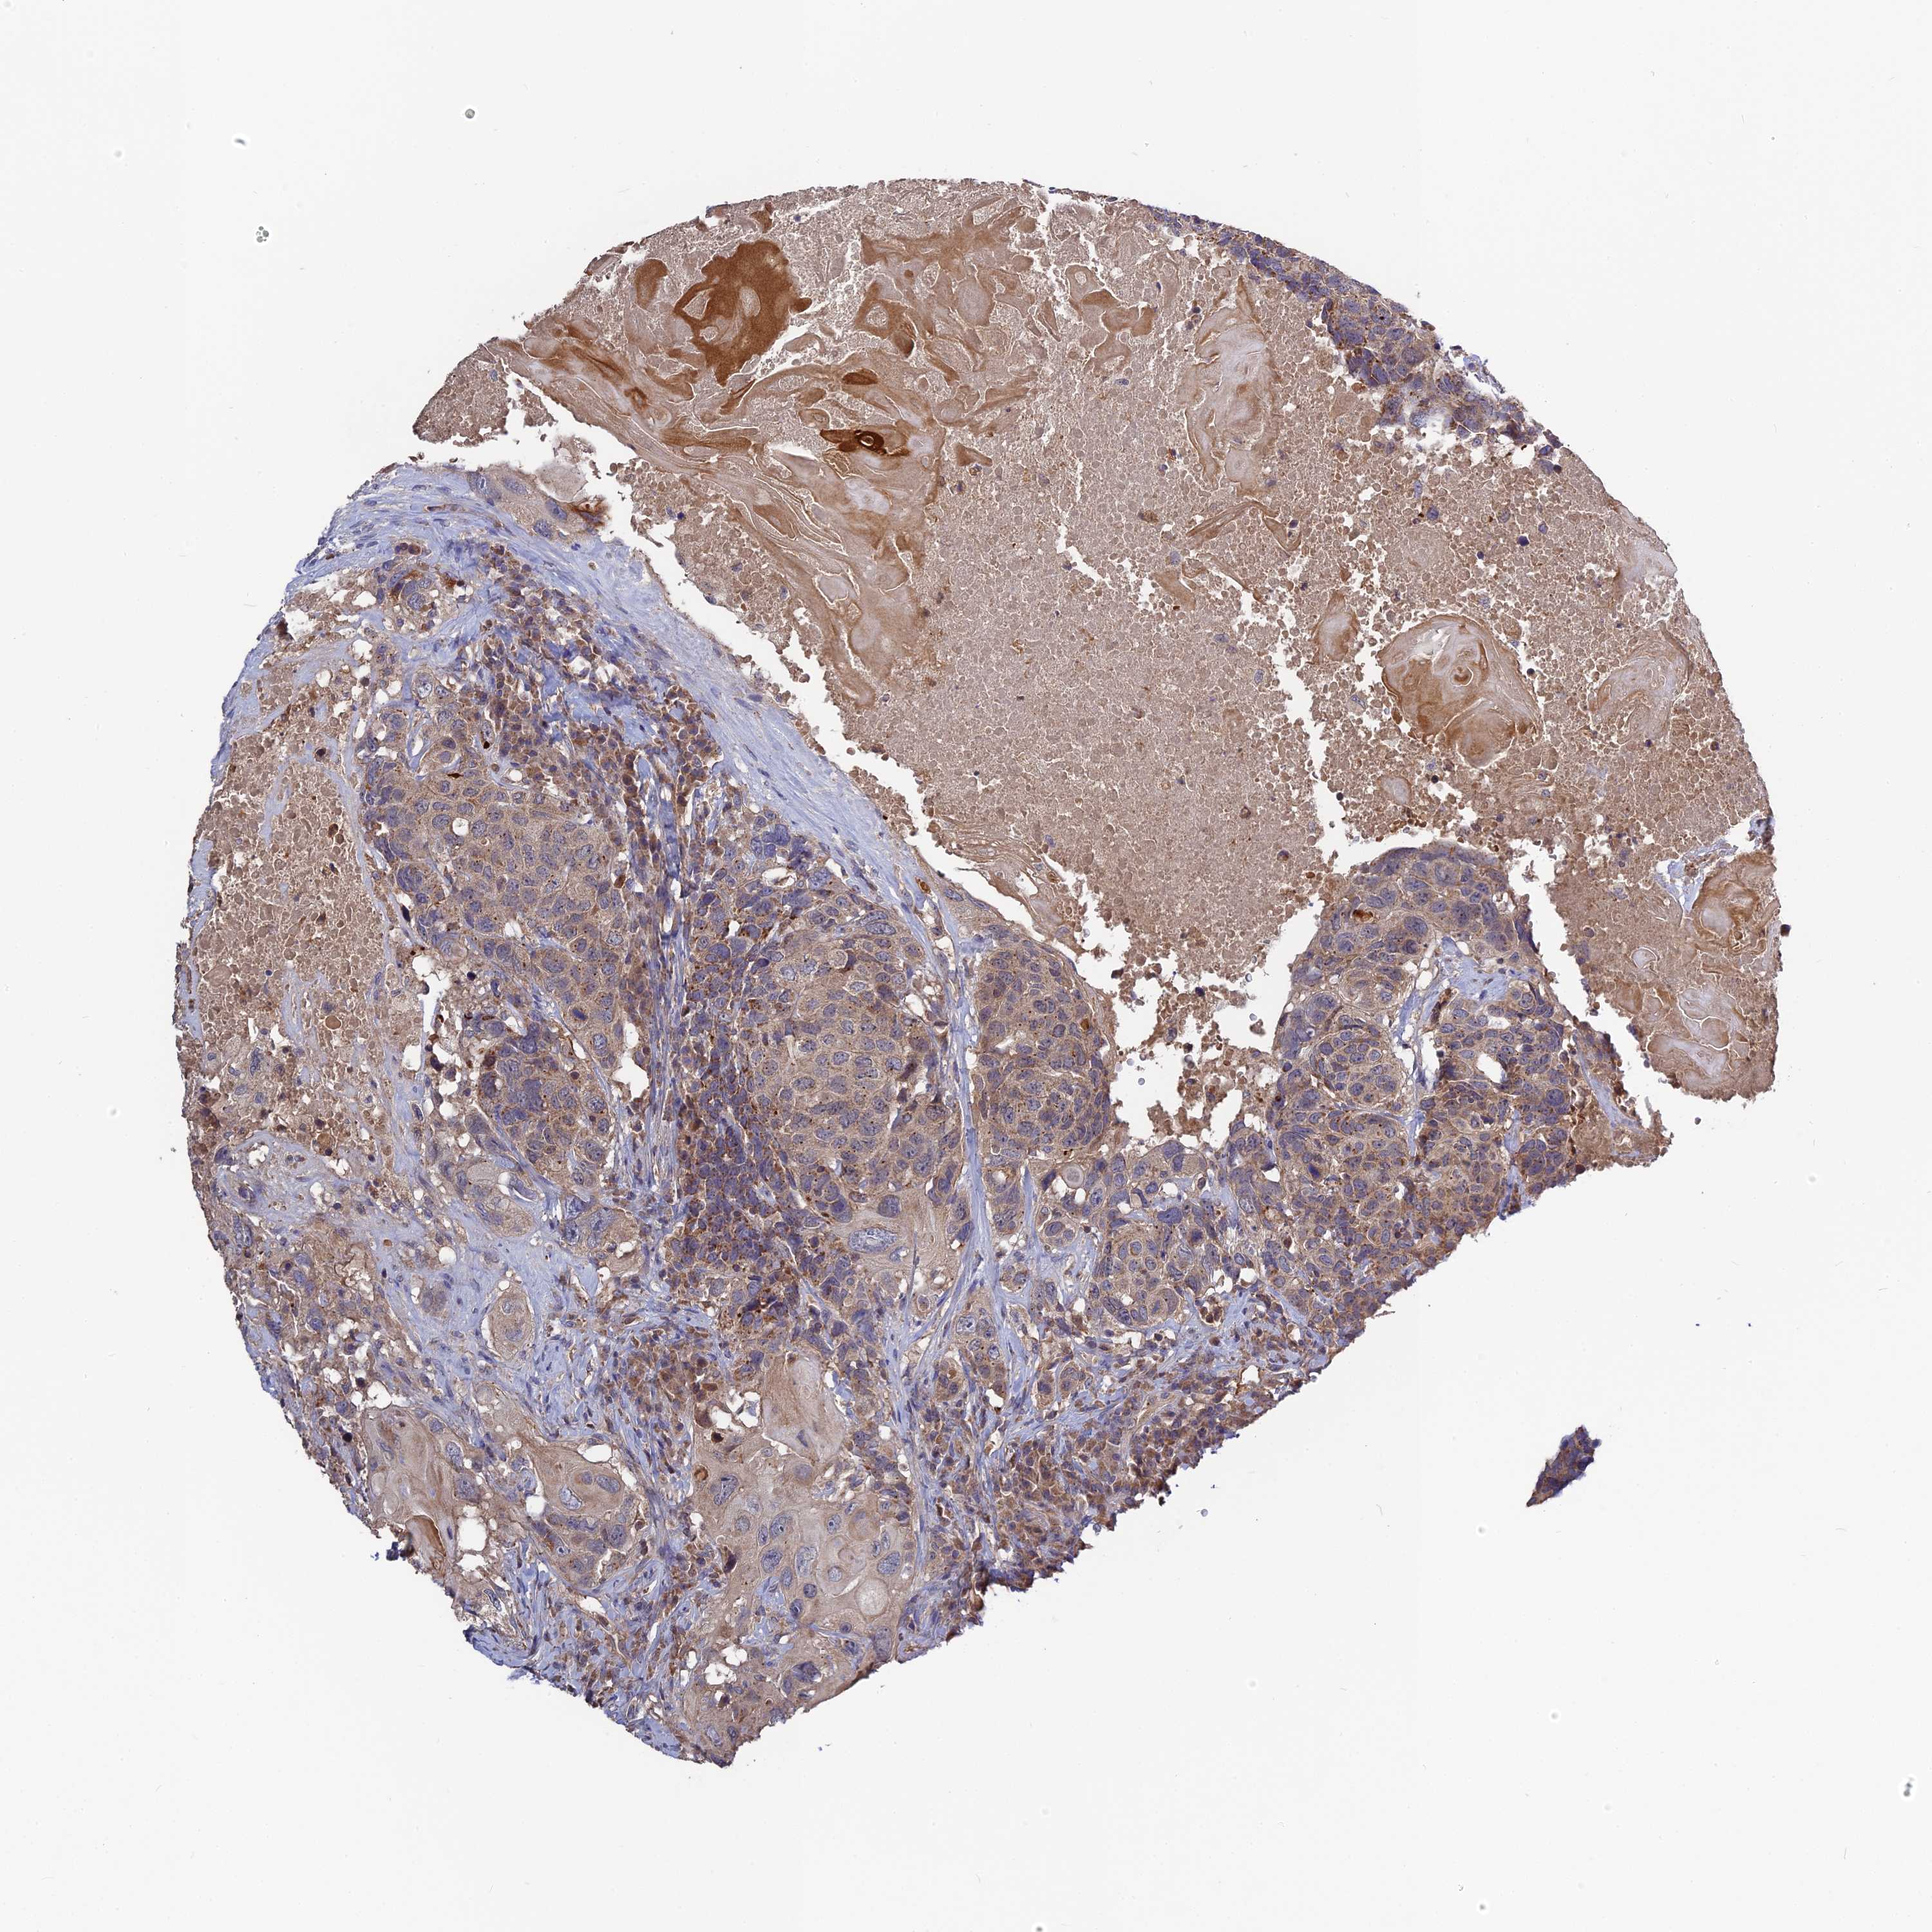

HEAD AND NECK CANCER - Protein expressioni

A mouse-over function shows sample information and annotation data. Click on an image to view it in a full screen mode. Samples can be filtered based on level of antibody staining by selecting one or several of the following categories: high, medium, low and not detected. The assay and annotation is described here.

Antibody stainingi

Antibody staining in the annotated cell types in the current human tissue is reported as not detected, low, medium, or high, based on conventional immunohistochemistry profiling in selected tissues. This score is based on the combination of the staining intensity and fraction of stained cells.

Each image is clickable and will lead to virtual microscopy that enables deeper exploration of all samples and also displays staining intensity scores, fraction scores and subcellular localization as well as patient and tissue information for each sample.

Antibody HPA042620

Staining

High

Medium

Low

Not detected

Intensity

Strong

Moderate

Weak

Negative

Quantity

>75%

75%-25%

<25%

None

Location

Nuclear

Cytoplasmic/membranous

Cytoplasmic/membranous,nuclear

Adenocarcinoma, NOS

Squamous cell carcinoma, NOS